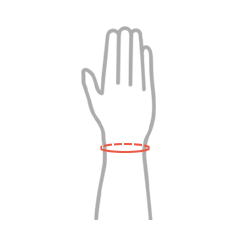

Tabela rozmiarów

| Rozmiar | Obwód nadgarstka | Sposób dokonywania pomiaru |

| S | 13-15 cm |  |

| M | 15-17 cm | |

| L | 17-19 cm | |

| XL | 19-21 cm |

Całkowita długość ortezy: 18 cm